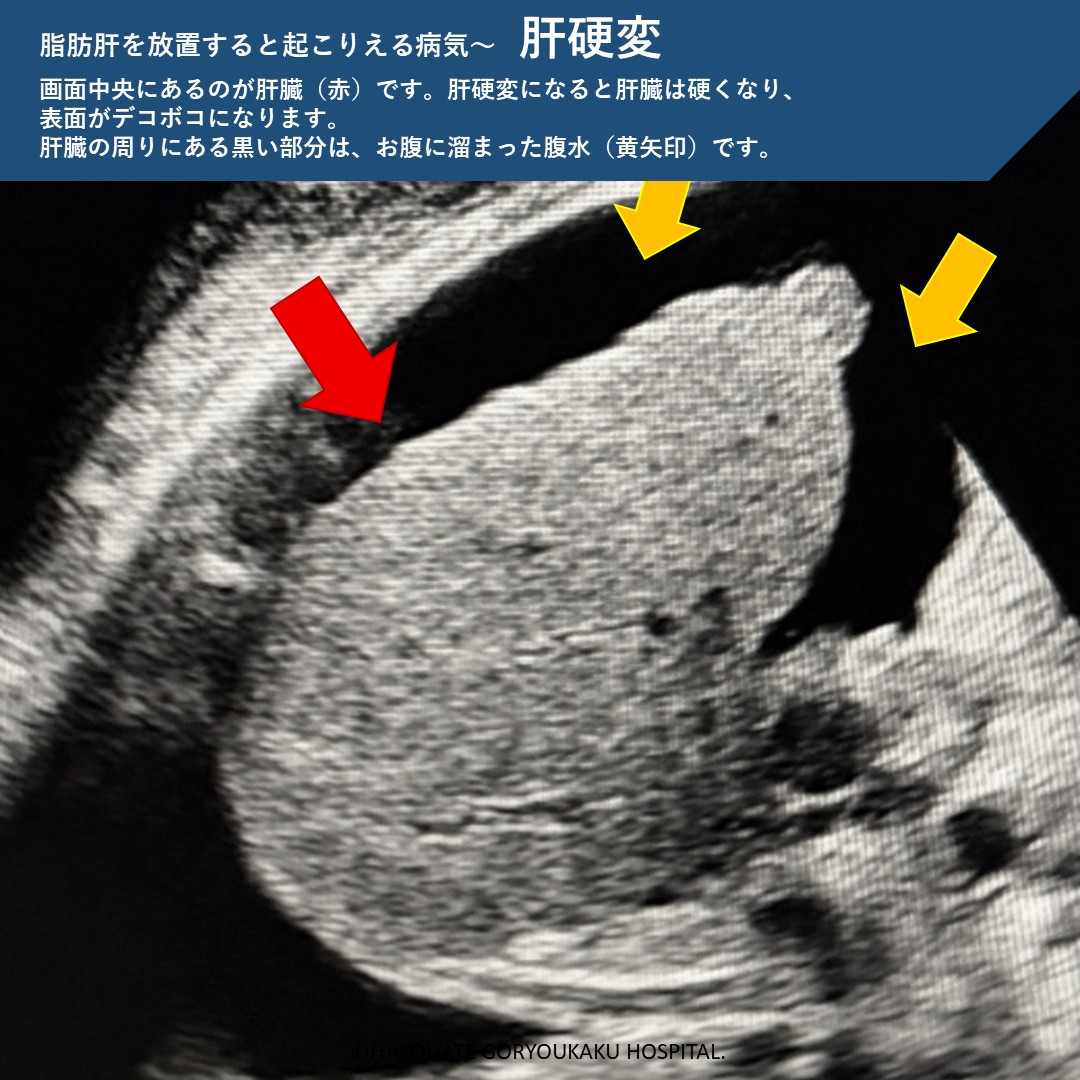

脂肪肝を放置すると

脂肪肝を放置すると、肝臓に炎症が起こり、やがて肝硬変に移行します。肝硬変になると肝細胞癌のリスクが上がります。また、こういった肝臓の病気だけでなく、心筋梗塞や脳卒中、肝臓以外の悪性腫瘍の原因にもなります。特に「メタボ+飲酒+脂肪肝」の組み合わせは、肝臓に関連する病気の死亡率や、肝細胞癌の発生リスクが高い事がわかっています。